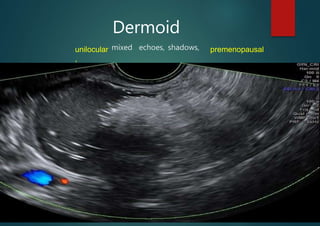

Dermoid

mixed echoes, shadows, premenopausal